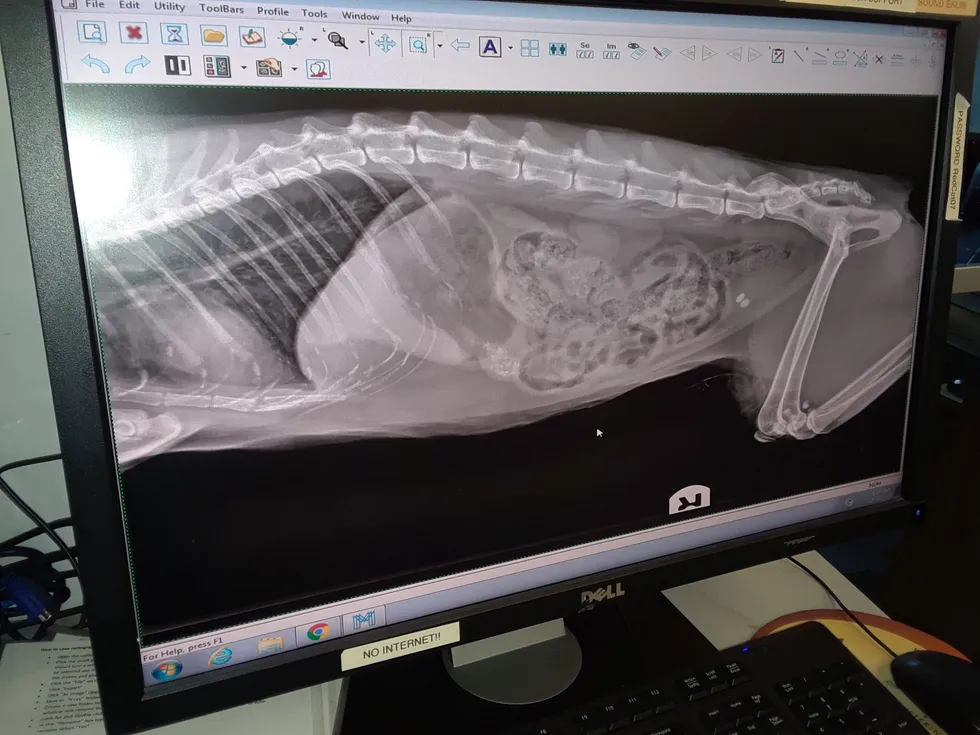

We have the latest DR (digital radiology) technology which has the x-ray plate embedded in the table and creates a digital image within 3 seconds of hitting the exposure button. We have a magnetic floating table to position the patient for more comfort.

DR images are the highest quality radiographs currently available and enable us to see the greatest details in the structures that we image. Radiographs are an excellent tool to assess the lungs,bones and joints. Computer programs allow the image to be processed further to zoom in to different areas or enhance or decrease contrast in the x-rays, similar to Photoshop for your vacation pictures.